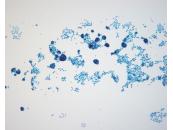

第38回日本臨床細胞学会九州連合会学会(熊本)スライドカンファレンス症例4

種別:泌尿器

出題:石原 明 潤和会記念病院病理診断科

| 年齢 | 70代 | 性別 | 男性 |

|---|---|---|---|

| 採取部位 | 尿 | 採取方法 | 自然尿 |

| 検体処理法 | LBC法(サイトリッチレッド、BD SurePath) |

臨床所見

既往歴:高血圧、心房細動、左鼠径ヘルニア手術。

現病歴:10ヶ月前 肉眼的血尿(主訴)、4ヶ月前 近医受診し、PSA値24.5、膀胱鏡にて前立腺部尿道の乳頭状

腫瘍指摘、当院紹介受診。

画像診断では左外鼠径・内外腸骨・総腸骨各リンパ節腫大。

臨床診断:前立腺癌・転移あり、尿道部尿路上皮癌。

| 正解 | 4. 前立腺導管型腺癌 |

▼選択肢及び投票結果

| 1.扁平上皮癌 | 0件 | (0.0%) | |

| 2. 尿路上皮癌 HGUC | 17件 | (16.3%) | |

| 3. 神経内分泌癌 | 0件 | (0.0%) | |

| 4. 前立腺導管型腺癌 | 84件 | (80.8%) | |

| 5. 前立腺尿道ポリープ | 3件 | (2.9%) | |

| 投票総数 | 104件 | (100%) |